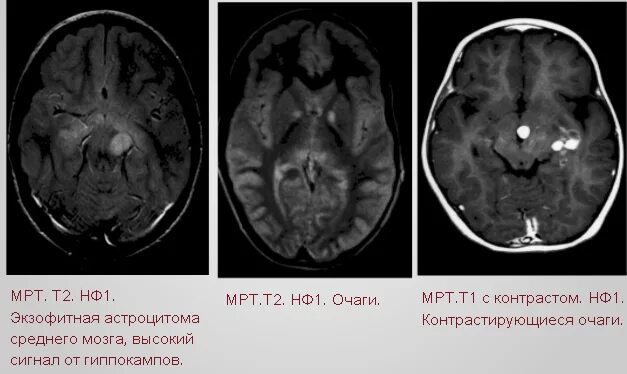

Нейрофиброматоз мрт